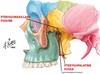

Tiny green area in anterior of skull here:

What bones make it up?

Foramen Caecum

- made up of alae of crista galli (of ethmoid) and frontal bone

- transmits emissary vein from nose to sup. sagittal sinus but is frequently closed

Jugular Foramen

- connects external base of skull to posterior cranial fossa